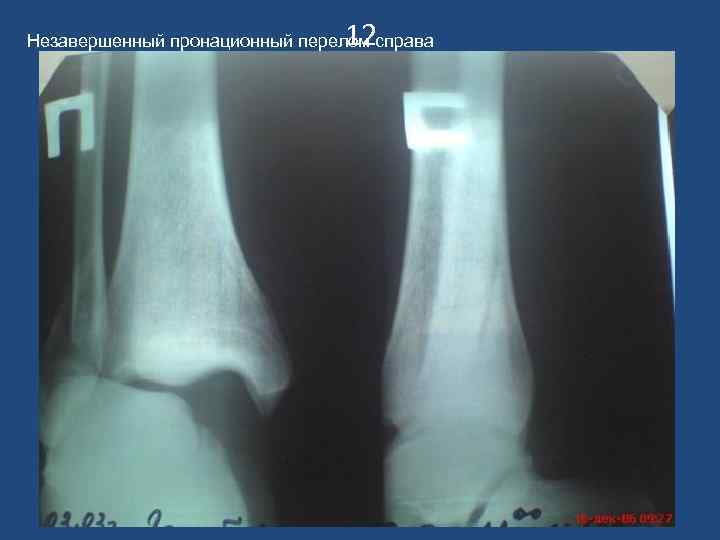

12 Незавершенный пронационный перелом справа